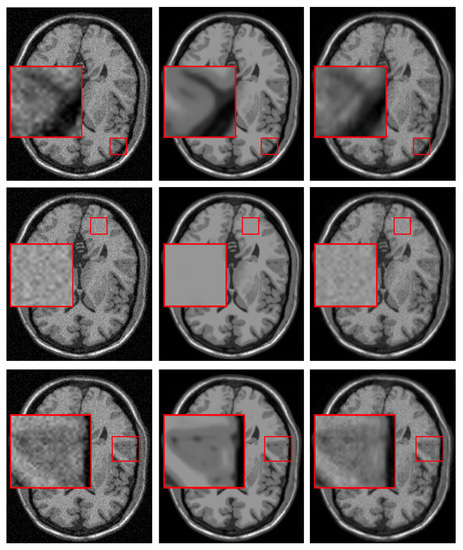

4.2.1. Synthetic Data

4.2.2. Real Data